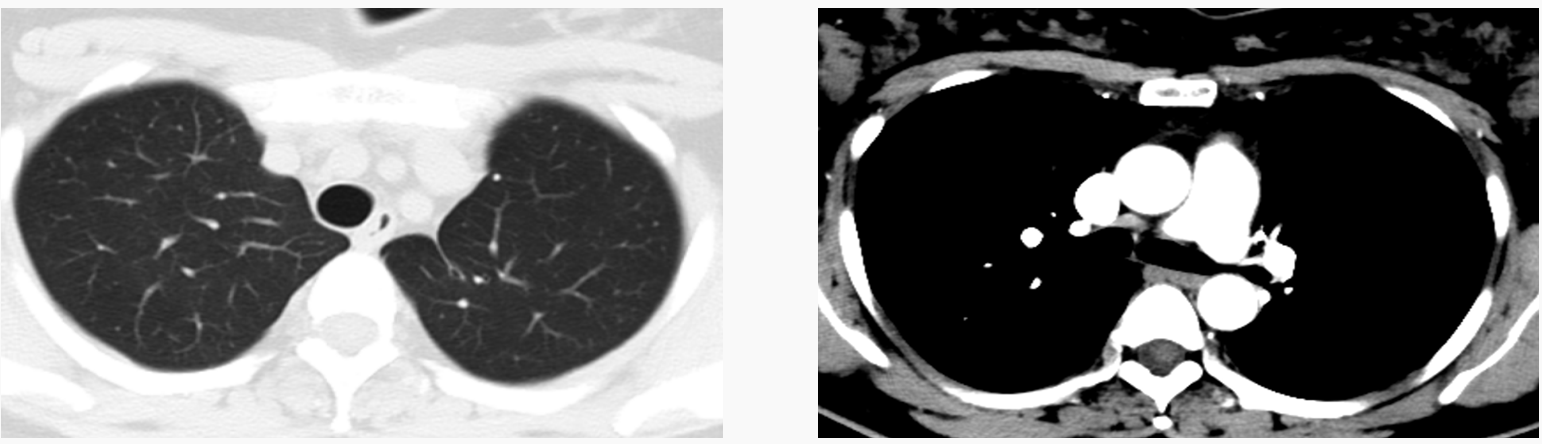

术后胸部CT:左肺上叶切除术后,相应左肺上叶支气管中断、其周围链状高密度灶及周围软组增厚。

1、左肺上叶切除术后,术区少许纤维灶,左侧膈肌及膈下腹腔内脏器位置上移,较前相仿。

2、左肺上叶前段及右上叶后段胸膜下小钙化灶,较前相仿。原双肺下叶磨玻璃小结节现显示欠清。

右肺多发实性微小结节,较前增多,部分为炎性病变可能。

3、右肺中叶、左肺下叶前内基底段少许炎症,右肺虫叶轻度支气管扩张,较前变化不大。